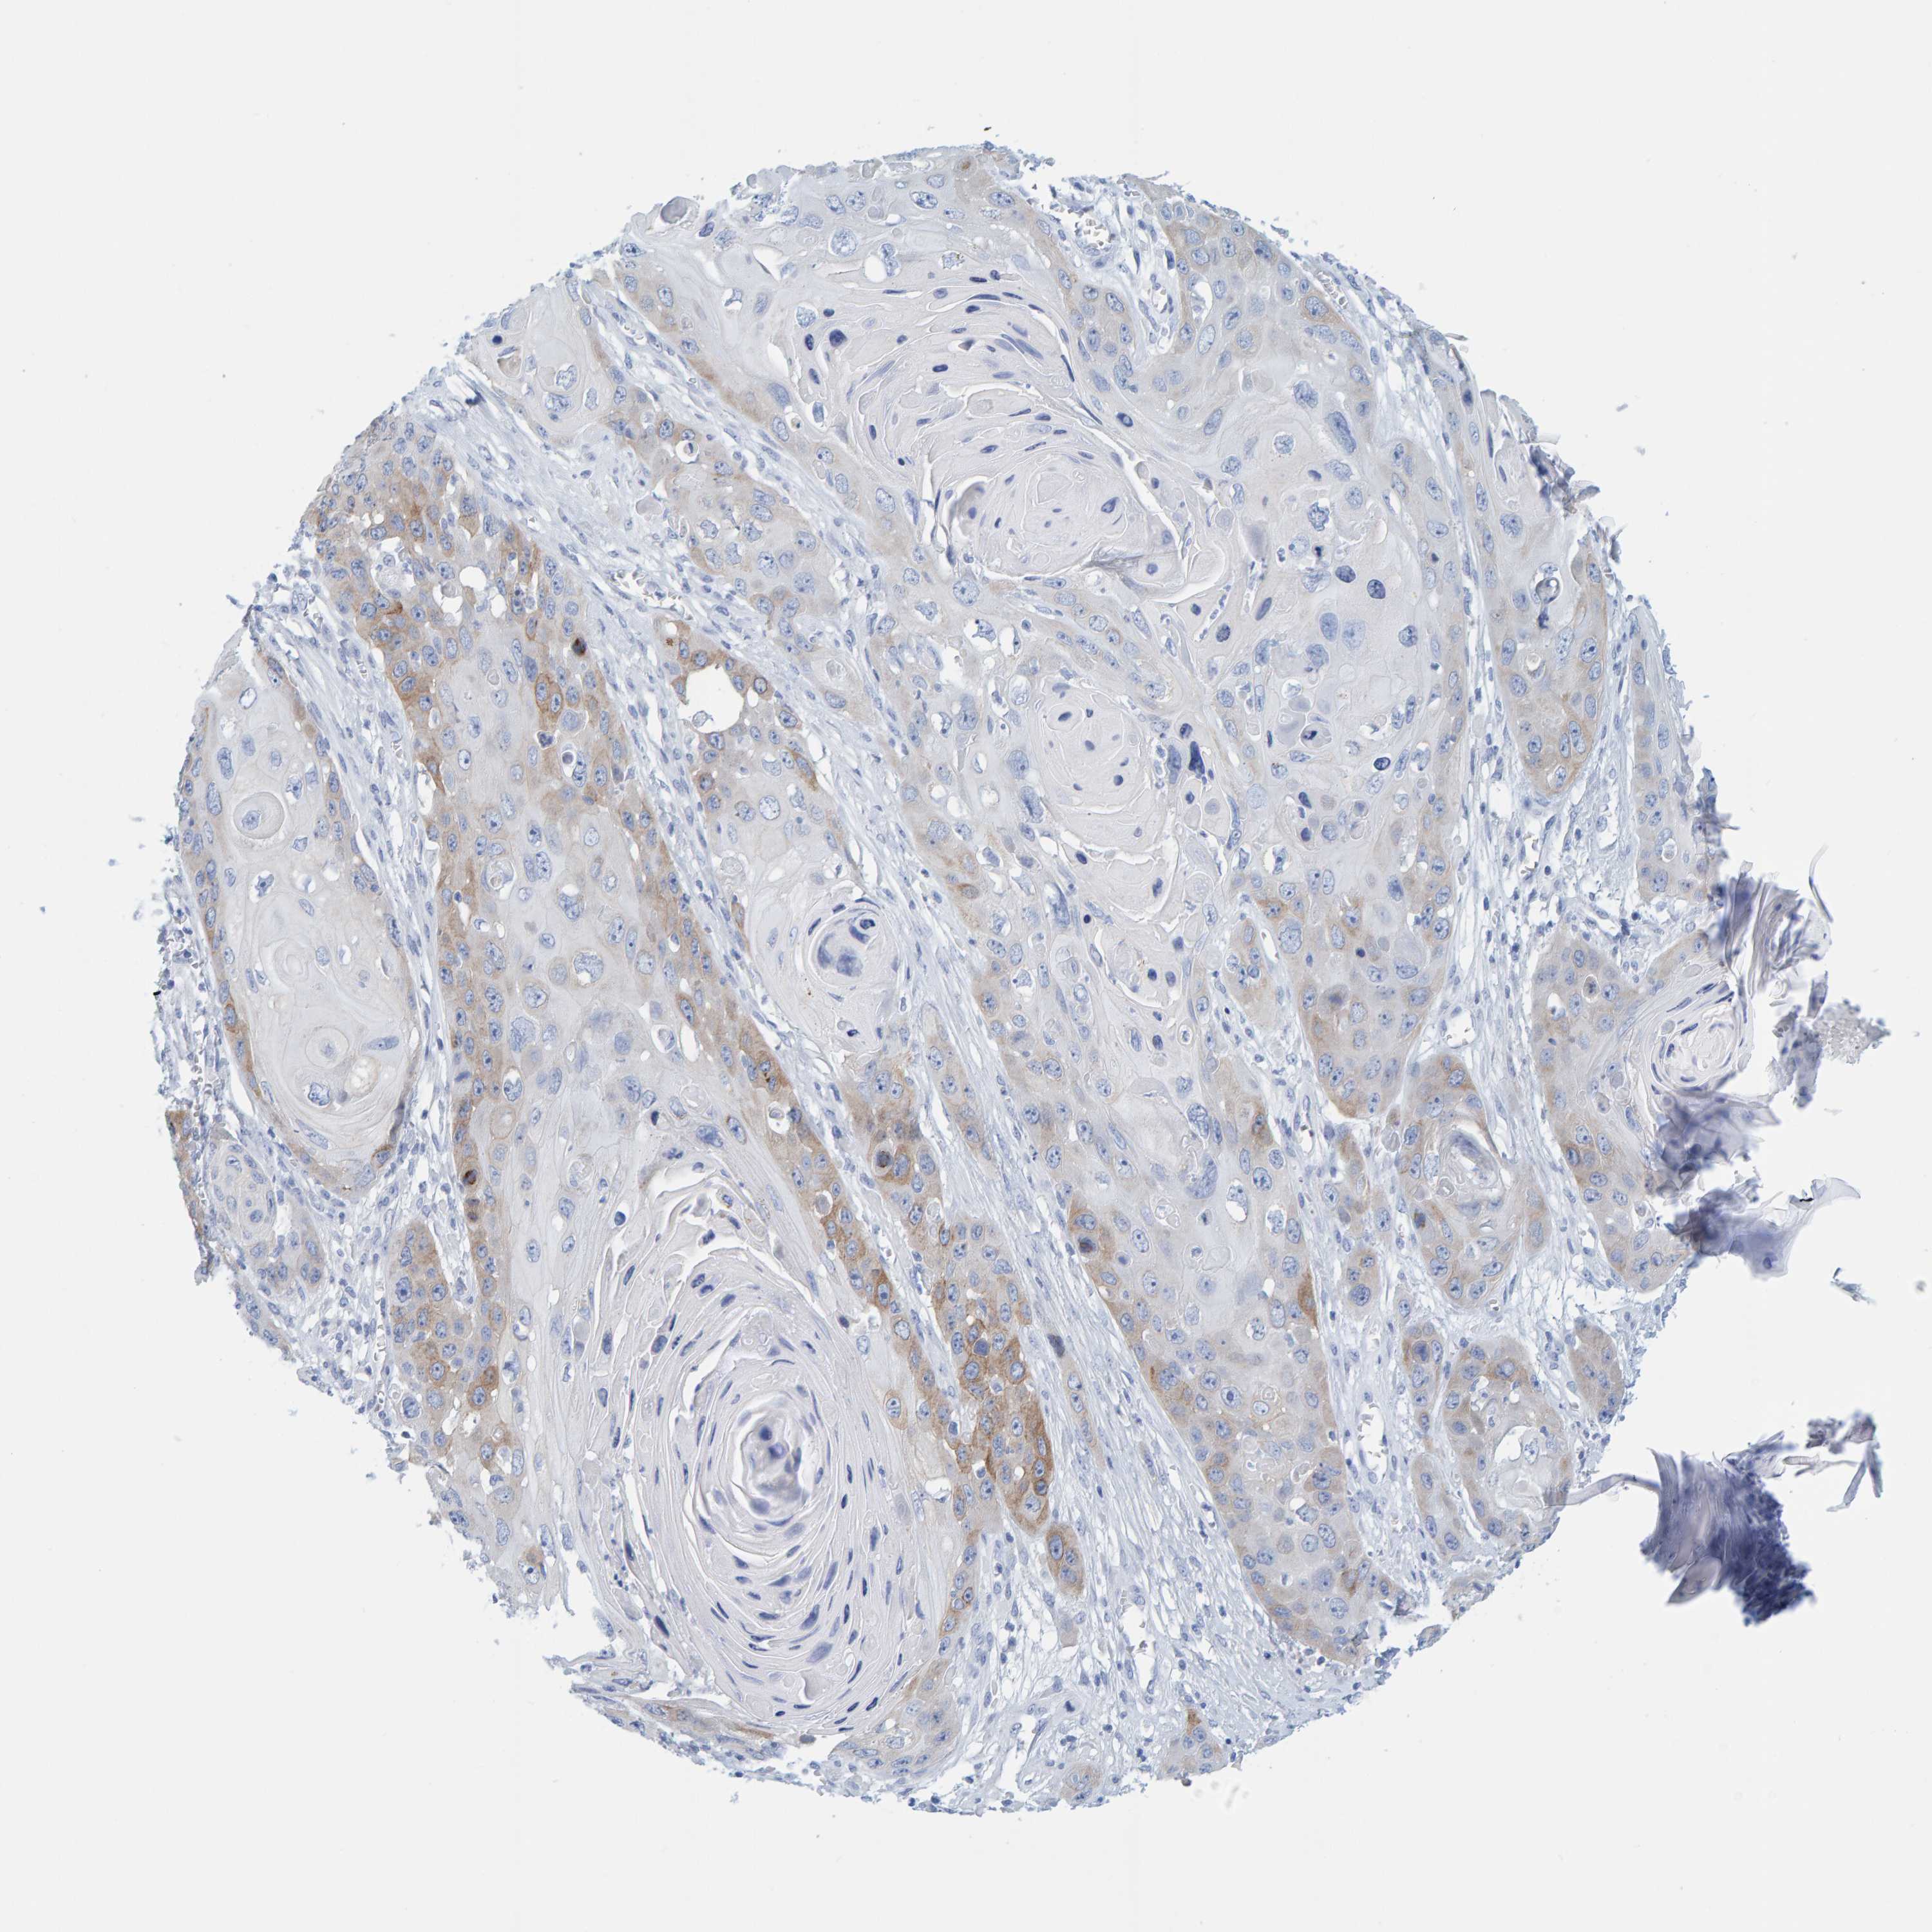

SKIN CANCER - Protein expressioni

A mouse-over function shows sample information and annotation data. Click on an image to view it in a full screen mode. Samples can be filtered based on level of antibody staining by selecting one or several of the following categories: high, medium, low and not detected. The assay and annotation is described here.

Antibody stainingi

Antibody staining in the annotated cell types in the current human tissue is reported as not detected, low, medium, or high, based on conventional immunohistochemistry profiling in selected tissues. This score is based on the combination of the staining intensity and fraction of stained cells.

Each image is clickable and will lead to virtual microscopy that enables deeper exploration of all samples and also displays staining intensity scores, fraction scores and subcellular localization as well as patient and tissue information for each sample.

Antibody HPA023021

Squamous cell carcinoma, NOS

Squamous cell carcinoma, metastatic, NOS